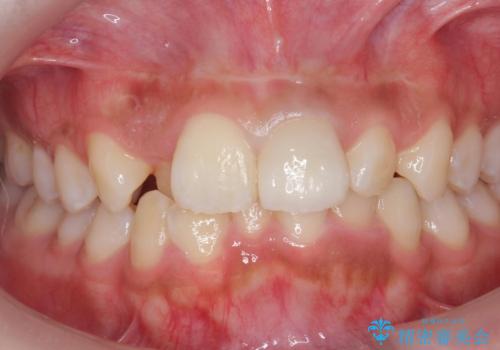

根の治療のやりかえは希望されなかったので土台だけやりかえを行い、ジルコニアクラウンで治療を行いました。

綺麗な被せ物が入り大変満足して頂けました。